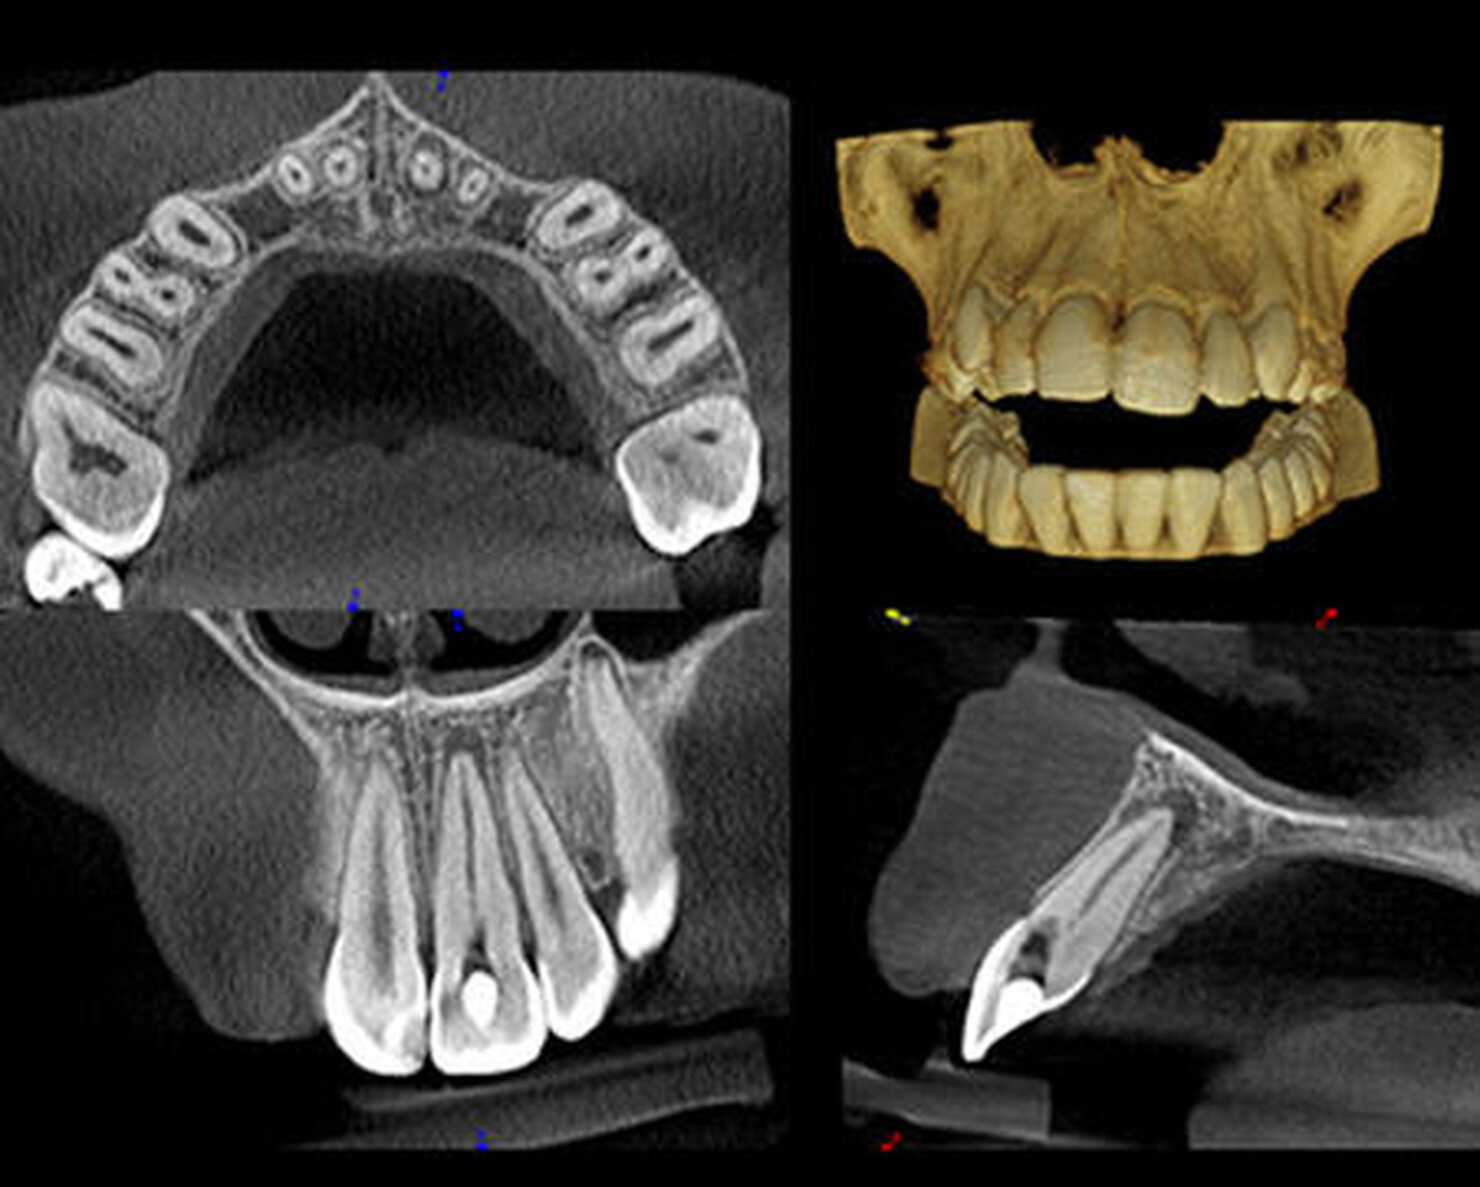

Il CS 8100 3D è progettato per l'accuratezza, con un generatore ad alta frequenza, un sensore CMOS 4T e un sistema di movimento esente da vibrazioni, che funzionano in sinergia per assicurare un'acquisizione precisa e regolare dell'immagine. Assicura immagini nitide, ad alto contrasto, con una risoluzione fino a 75 μm. Le immagini 3D presentano viste più accurate delle anatomie dentali dei pazienti. Si visualizza l'area d'interesse da ogni angolo e le immagini 3D eliminano le sovrapposizioni e le distorsioni.

Dagli esami panoramici tradizionali, all'endodonzia, alla pianificazione degli impianti e alle applicazioni di chirurgia orale, il CS 8100 3D offre capacità molto maggiori rispetto alla media dei sistemi 3D. Una tecnologia 2D che è stata premiata e che produce eccellenti immagini panoramiche in pochi secondi. Le immagini 2D e 3D si complementano e migliorano le capacità diagnostiche. Le rappresentazioni 3D accurate assicurano diagnosi accurate. Le funzionalità CAD/CAM permettono di eseguire un maggior numero di procedure presso lo studio.